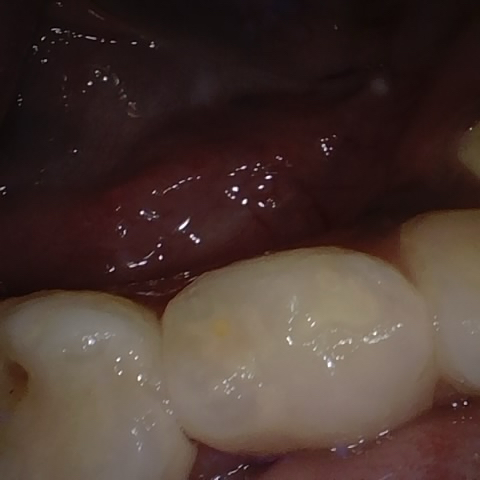

Annotated as "Good"